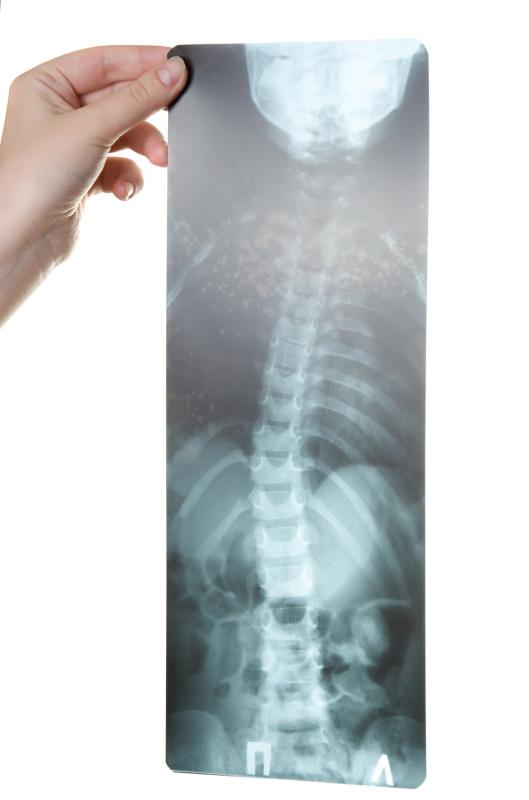

Anorexia is complicated by low BMD, and patients with the psychiatric disorder exhibit low bone formation as well as high bone resorption rates, Haines pointed out. This puts the patients at risk of developing fractures. “The spine, particularly its trabecular component as measured by lateral spine dual-energy x-ray absorptiometry, is most severely affected.”

In her presentation, Haines noted that mean postero-anterior (PA) spine at month 12 showed the biggest gain with sequential therapy (p=0.03), with a trend toward being higher with risedronate alone (p=0.08), when compared with placebo. On the other hand, mean lateral spine aBMD was higher in the sequential therapy group than in either groups (p=0.002 and p=0.04, respectively). [ENDO 2021, abstract OR06-1]

From baseline to 12 months, mean PA and lateral spine aBMD increased markedly by 1.9 percent and 4.2 percent on sequential therapy (p<0.05), both by 1.7 percent on risedronate (not significant), and dropped by 0.3 percent and 1.1 percent on placebo, respectively.